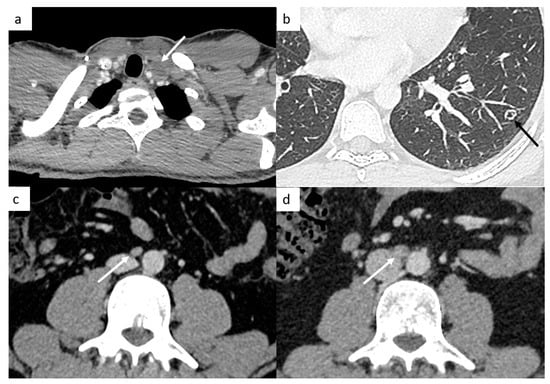

It is very important to examine the left supraclavicular region, because it is a classic localization of lymph nodes and is often missed because of artifact shoulders (Figure 4).

Figure 4.

Small disease. Thoracic CT reveals a small left supraclavicular lymph node ((a), arrow). Lung metastases can appear as different features such as small nodules which may be excavated (b). Abdominal CT demonstrates a small interaorticocaval lymph node (c) and the repetition of the CT 6 months later shows an increasing size of this lymph node, a finding indicative of involvement (d).

Positive Lymph Nodes

TGCT have a high spread to micrometastatic lymph nodes; therefore, even if the size is under the cut-off, radiologists need to analyze morphologic features such as the shape (round or spiculated) and the enhancement (heterogeneous, central necrosis), which suggest positive lymph nodes (Figure 4).

4.1.3. Different Features of Lung Metastases

Most of the time, they appear as multiple small nodules in TGCT. However, lung metastases can appear as different features such as pulmonary miliary disease, small excavated nodules or irregular nodules (Figure 4), and it can be complicated to distinguish metastases from infection or granulomatosis disease. Perifissural lung micronodules are most of time considered as intrapulmonary lymph nodes, but in advanced disease, they can be metastatic disease with lymphatic spread.